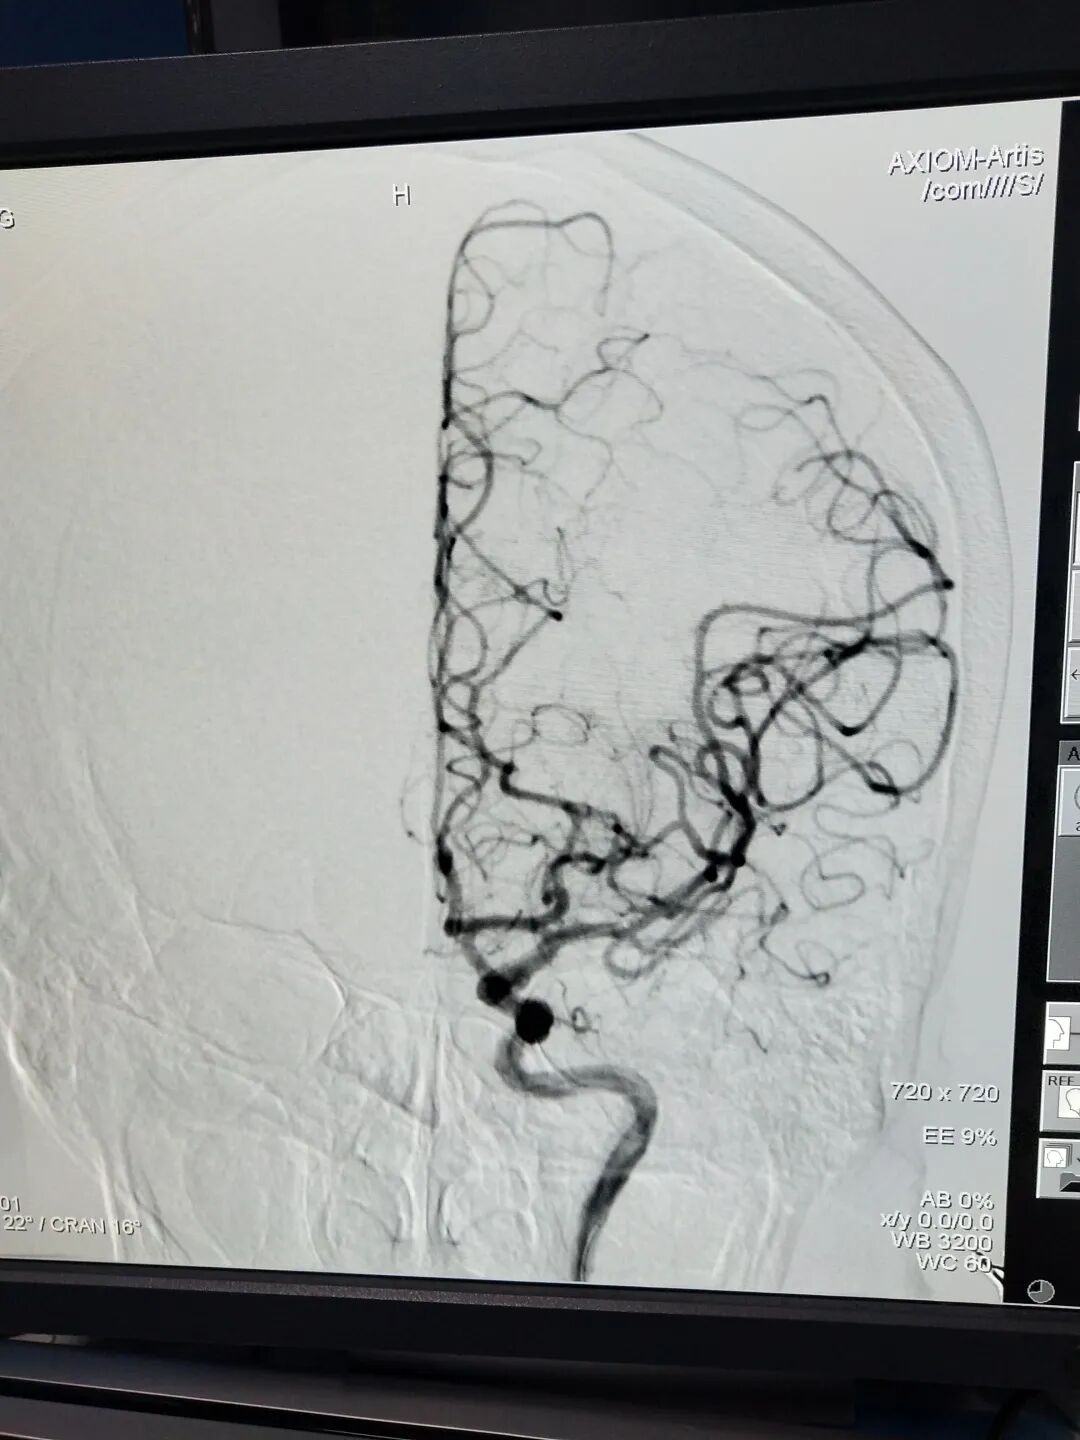

术后M2完全再通

经验丰富的应诊医生、训练有素的接诊护士、优先住院的医院政策、清晰易辨的各种标识、快速准确的影像分析……卒中绿色通道的便捷有序、医护人员的有条不紊,使患者及家属对医院充分信任,毫不犹豫的签字同意介入治疗。造影见左侧大脑中动脉M2段闭塞,予尿激酶动脉溶栓患者血管血流恢复通畅,整个过程仅仅花去了1小时。